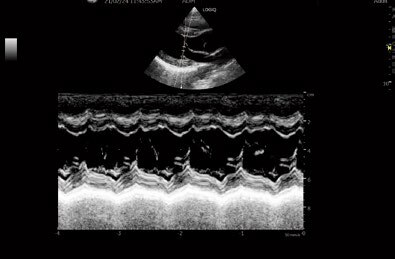

Anatomical M-Mode

様々な角度でMモードを生成。条件の悪いビューに

ピンポイントであわせることが可能です。

検査後、Bモード保存動画からのMモード生成も可能です。